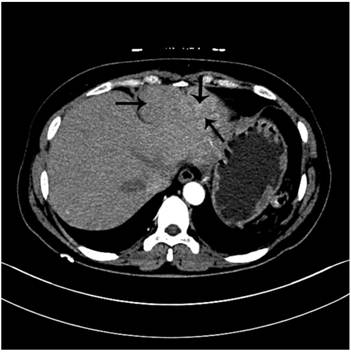

Figure 1

Non-contrast CT scan shows three masses at the surface of liver mimicking tumors of left lateral lobe.

A 49-year-old female patient complained of subxiphoid pain with fatigue for half a month. The patient reported history of trauma and splenectomy which was performed 20 years ago. On physical examination no positive sign was noted. She was admitted into our hospital for further work up because abdominal mass was found by ultrasound in local hospital. The patient had no family history of related diseases. Then the patient underwent regular preoperative laboratory test in our hospital. Her white blood cell was 7.2×109/L (reference rang 4x109/L -10x109/L), haemoglobin was 116g/L (reference range 110 g/L -150 g/L), blood platelet was 129×109/L (reference range 100×109/L -300×109/L). The results of prothrombin time (PT), activate part blood coagulation time (APTT), thrombin time (TT), fibrinogen (FIG) and live function test (LFT) were in normal range. AFP is in normal range. Both hepatitis B and C virus test were negative. EKG and CXR were both normal. Contrast CT imaging (Figure 1,2) demonstrated multiple space-occupying masses of liver and colon which were considered as malignant tumors.